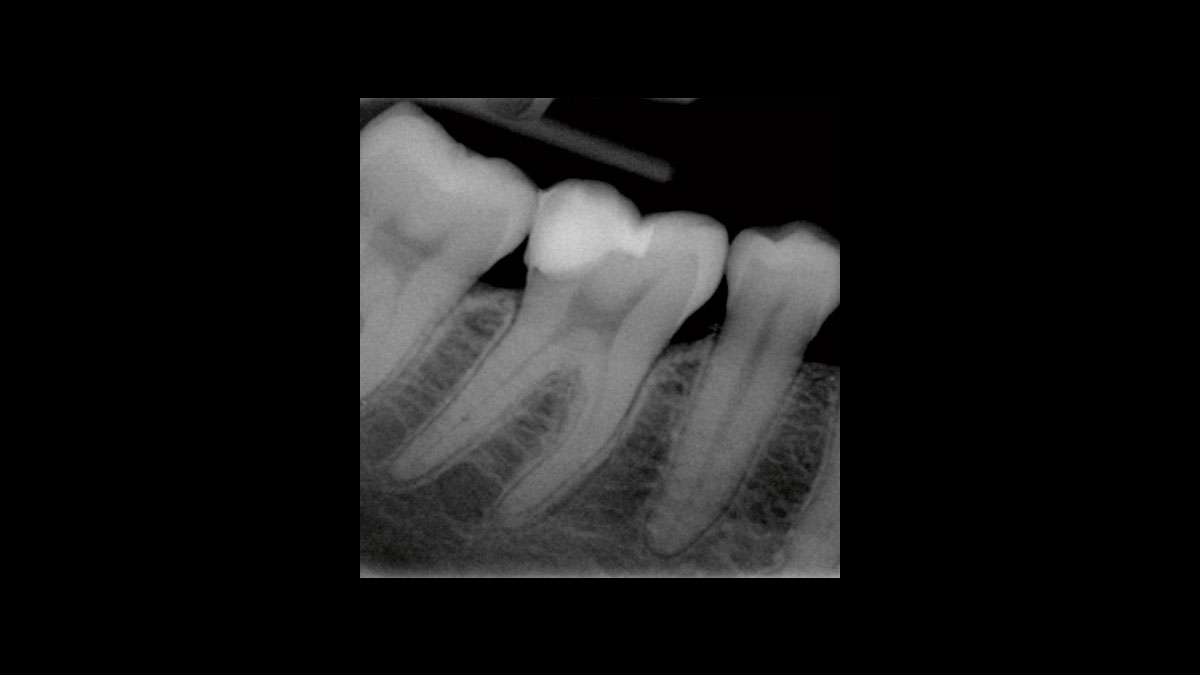

Periodoncia

Las siguientes aplicaciones se presentan en los videos y las imágenes:

• Reducción de gérmenes en periodoncia

Reducción de gérmenes en periodoncia